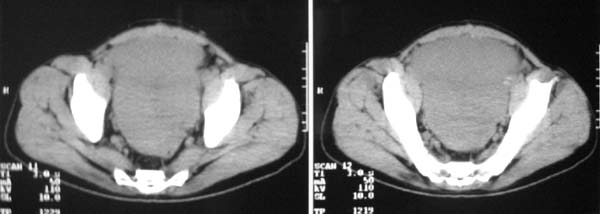

以下是引用zjzjr在2007-9-27 22:20:00的发言:[br]肠腔受推移,未见明显扩张及液平,所以考虑是肠外病灶, 间叶源性肿瘤?脂肪瘤?建议增强。

以下是引用guzhongliangddd在2007-9-27 23:21:00的发言:[br][br]与肠内高密度相同,病灶应该没有钙化,我认为首先考虑是间叶组织的良性肿瘤。建议楼主做后重建观察。中线区域大血管旁未见确切增大淋巴结。病灶对肠道只是推移关系。

以下是引用余辉在2007-9-27 22:24:00的发言:[br]暂考虑肠道间质来源肿瘤如小肠平滑肌肉瘤/瘤可能,应该增强